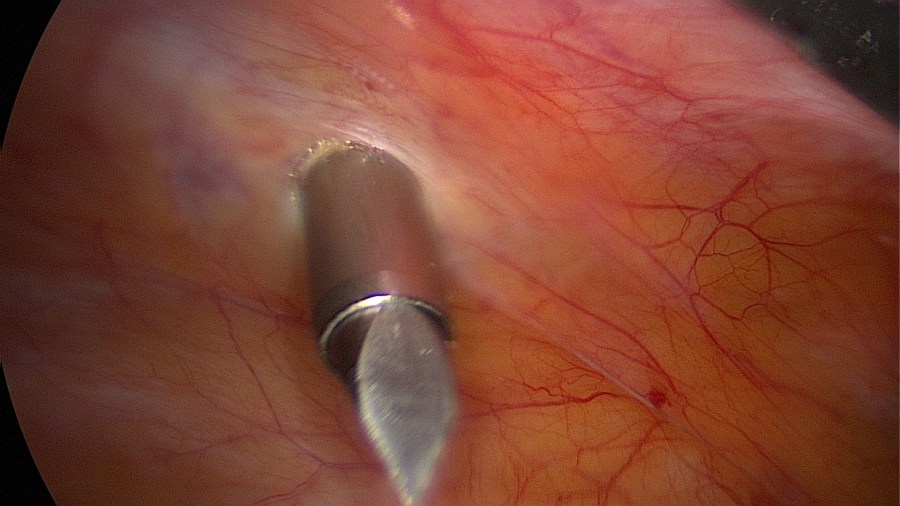

Gain intraperitoneal access and ensure adequate visualization of the small pelvis.

Linear salpingotomy: open the tube directly over the tubal pregnancy with a straight incision made with a monopolar needle (Taran, F-A et al., 2015).